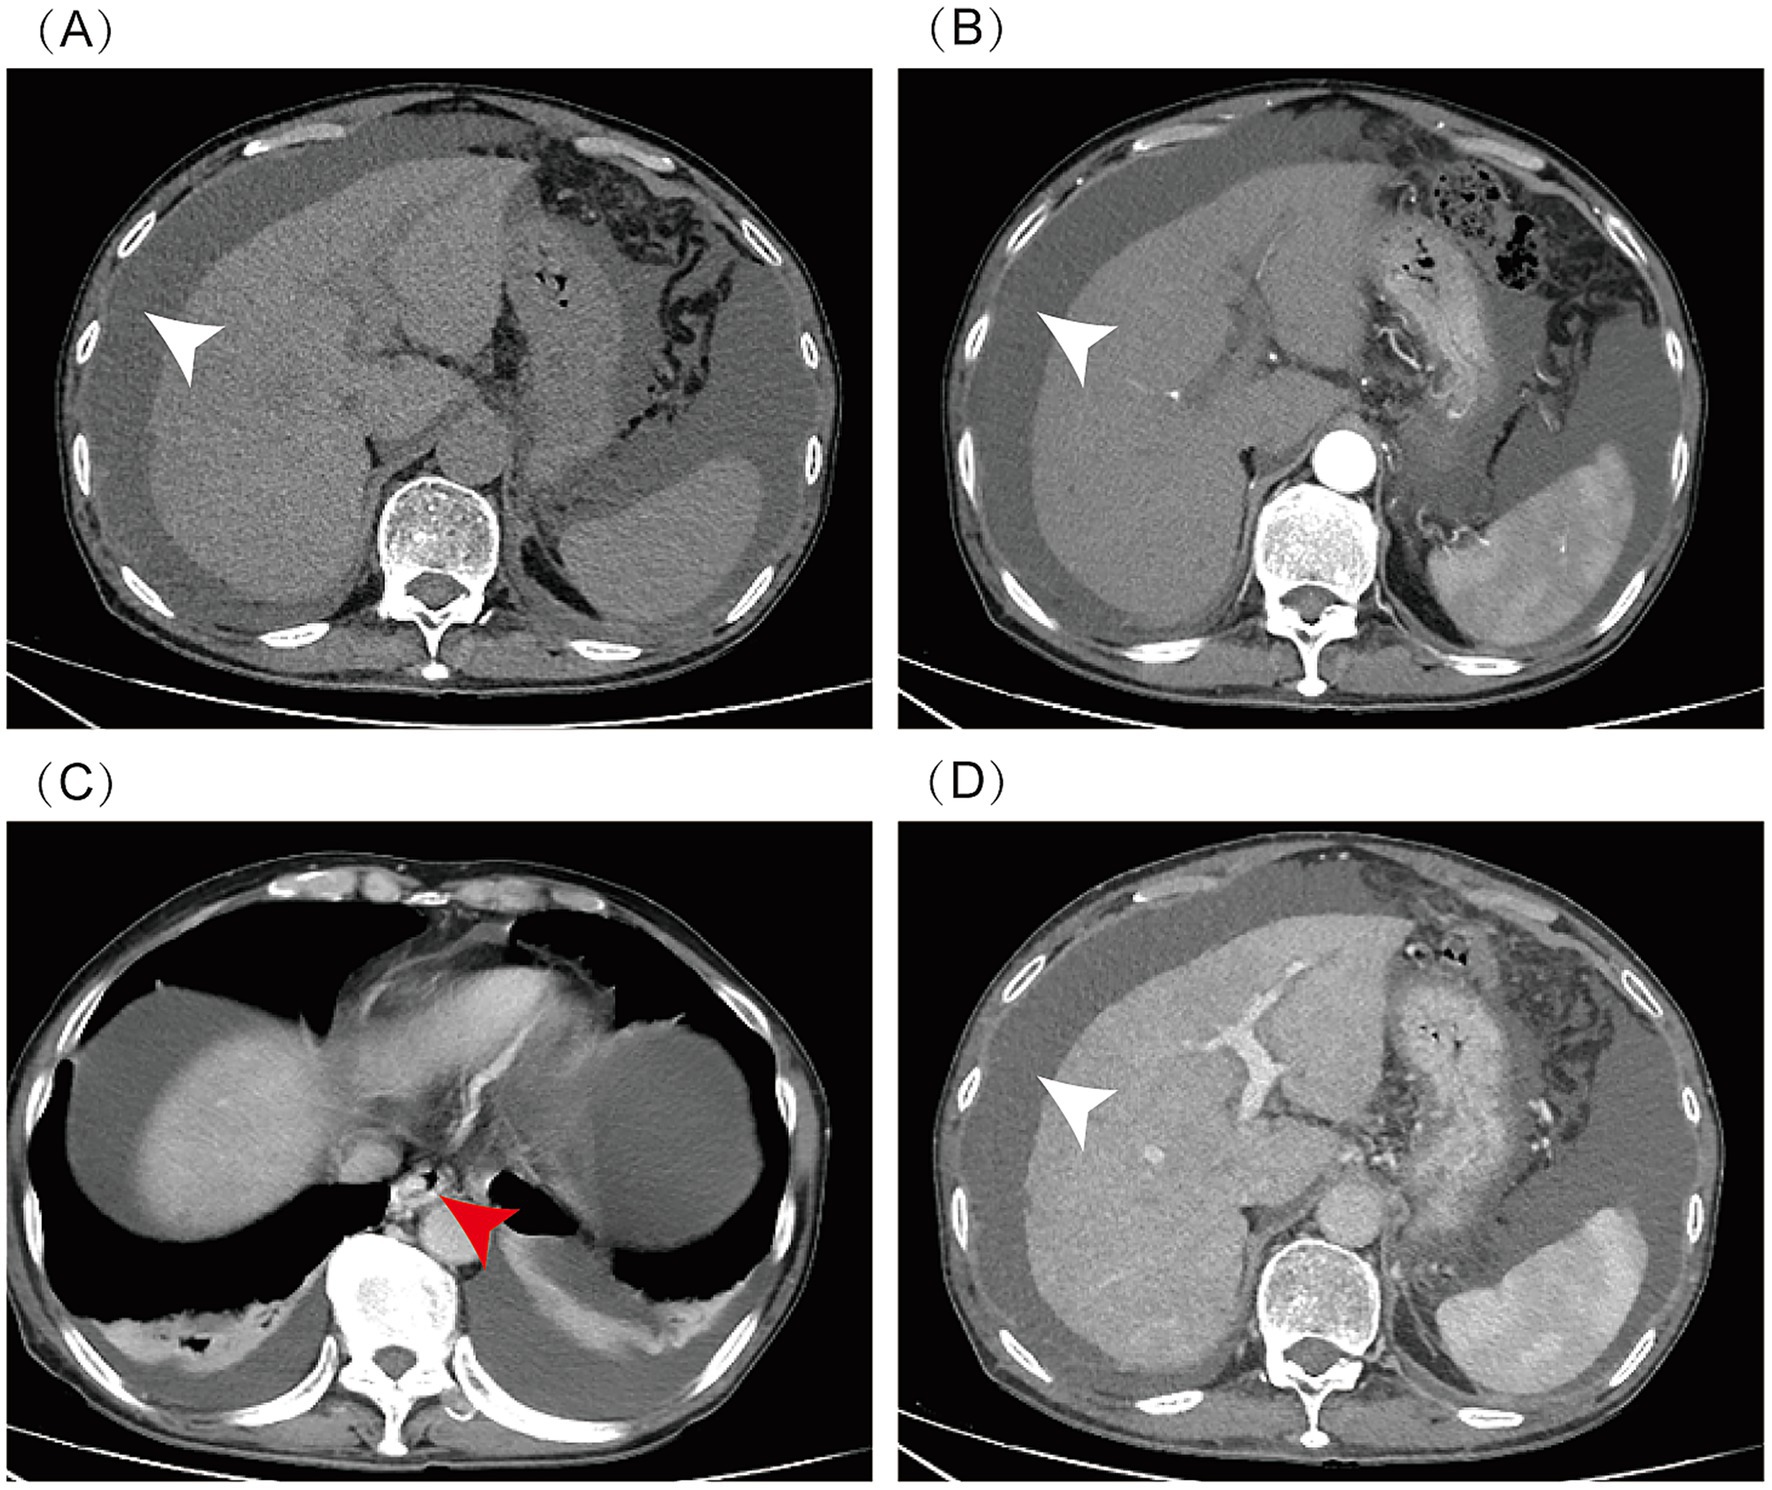

In November 2024, a 73-year-old man was admitted to our hospital with the chief complaint of “abdominal distension for over half a month.” The patient had a 50-year history of chronic alcohol abuse (daily alcohol intake of 250 g), primary biliary cholangitis (PBC, AMA-M2 positive), and a 1-year history of consuming Gynura segetum-infused alcohol. Laboratory examinations showed alanine aminotransferase (ALT) of 14.7 U/L, aspartate aminotransferase (AST) of 54.5 U/L, alkaline phosphatase (ALP) of 286.4 U/L, γ-glutamyl transferase (GGT) of 697.7 U/L, lactate dehydrogenase (LDH) of 305 U/L, total bilirubin of 80.3 μmol/L, direct bilirubin of 29.7 μmol/L, albumin of 38.2 g/L, blood ammonia of 35.9 μmol/L; prothrombin time of 13.8 s, international normalized ratio (INR) of 1.21; and anti-AMA-M2 antibody positive (+). Enhanced abdominal computed tomography (CT) revealed cirrhosis, massive ascites, dilated portal vein, esophageal and gastric varices, and hepatic steatosis (Figure 1). Upper gastroscopy showed grade II–III esophageal varices and portal hypertensive gastropathy. Ascites examination: ascitic fluid somatic cell count (AF-SCC) 340 × 106/L, total protein 21.3 g/L, albumin 13.8 g/L, and adenosine deaminase 4.6 U/L. The patient was managed with complete alcohol abstinence and received a combination of diuretic therapy, ursodeoxycholic acid, and carvedilol. Following symptomatic treatment with clinical improvement in abdominal distension, the patient was discharged.

Figure 1

Abdominal enhanced CT: massive ascites (indicated by white arrow), cirrhosis, esophageal and gastric varices (indicated by red arrow), and hepatic steatosis. CT scan phases: (A) Non-contrast, (B) Arterial, (C) Venous, (D) Delayed.